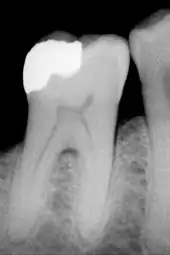

L'émail dentaire est une structure minéralisée d'origine épithéliale qui recouvre la couronne dentaire des vertébrés actuels et fossiles afin de la protéger des différentes agressions. L'amélogenèse (ou formation de l'émail) est assurée par les améloblastes (en), cellules sécrétrices qui sont détruites lors de l'éruption de la dent dans la cavité buccale. L'émail ne pouvant se régénérer en cas d'altération, il est doté par compensation d'une organisation tridimensionnelle complexe et d'un fort degré de minéralisation, qui en fait la structure la plus dure et la plus résistante de l'organisme, d'où son intérêt en médecine légale et en paléontologie. L'émail est la structure dentaire (et non le tissu car celui ci n'est pas vascularisé, ni innervé mais minéralisé, bien que très souvent même en clinique on parle de tissu amélaire)[1] normalement visible, supporté par une couche sous-jacente de dentine. Avec la dentine, le cément et la pulpe dentaire, il constitue un des quatre principaux tissus qui constituent la dent.

L'émail est composé de trois phases : la phase minérale représente 93-96 % en poids[2], la phase organique 0,4-5 %[3] et la phase aqueuse 3-7 % (le pourcentage d'eau étant en moyenne de 12 % pour la dentine et 33 % pour l'os)[4]. Sa partie minérale est principalement composée d'un réseau de cristaux d'hydroxyapatite (Ca10(PO4)6(OH)2). Le fort pourcentage de minéraux dans l'émail est responsable non seulement de sa rigidité et de sa dureté, supérieure à celle du tissu osseux, mais aussi de sa friabilité. La dentine, qui est moins minéralisée et moins friable, est indispensable comme support et compense les faiblesses de l'émail.

La couleur de l'émail va du jaune au gris clair. Comme l'émail est semi-translucide et opalescent, la couleur jaune orangée de la dentine (ou de tout matériau de réparation dentaire) sous l'émail affecte fortement l'apparence de la dent.

L'émail varie en épaisseur sur la surface de la dent. Il est plus épais au niveau du sommet de la couronne dentaire (plus de 2,5 mm) et plus mince sur la jonction émail-cément (JEC).